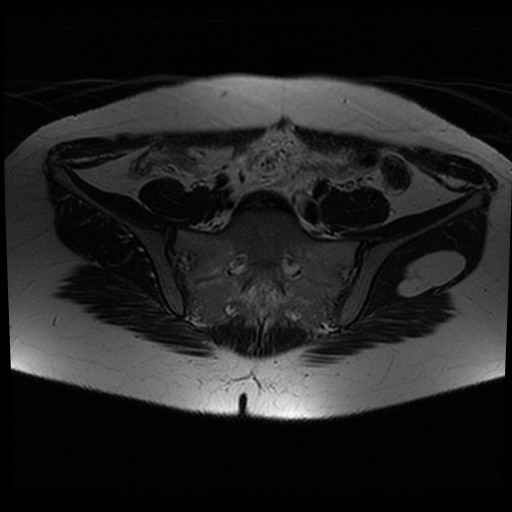

bekken